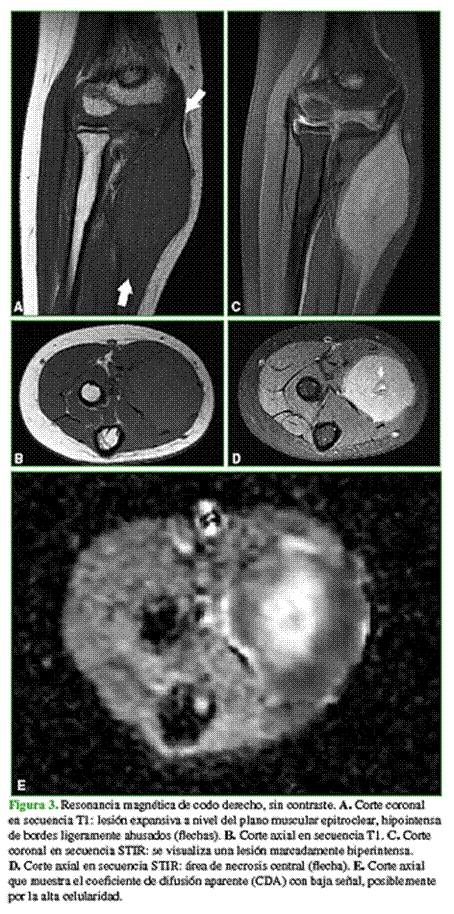

En la resonancia magnética, se visualiza una lesión hipointensa en secuencia T1 (Figura 3A y B) e hiperintensa en secuencias T2 y con supresión grasa (Figura 3C y D), en el interior del plano muscular epitroclear, de bordes ligeramente definidos. No se logra identificar compromiso óseo.

En las secuencias de difusión, se comporta hiperintensa, con baja señal en el coeficiente de difusión aparente en el sector periférico (valor promedio 0,7 x 10-3 mm2/s) planteando la posibilidad de una lesión con alta celularidad (Figura 3E).